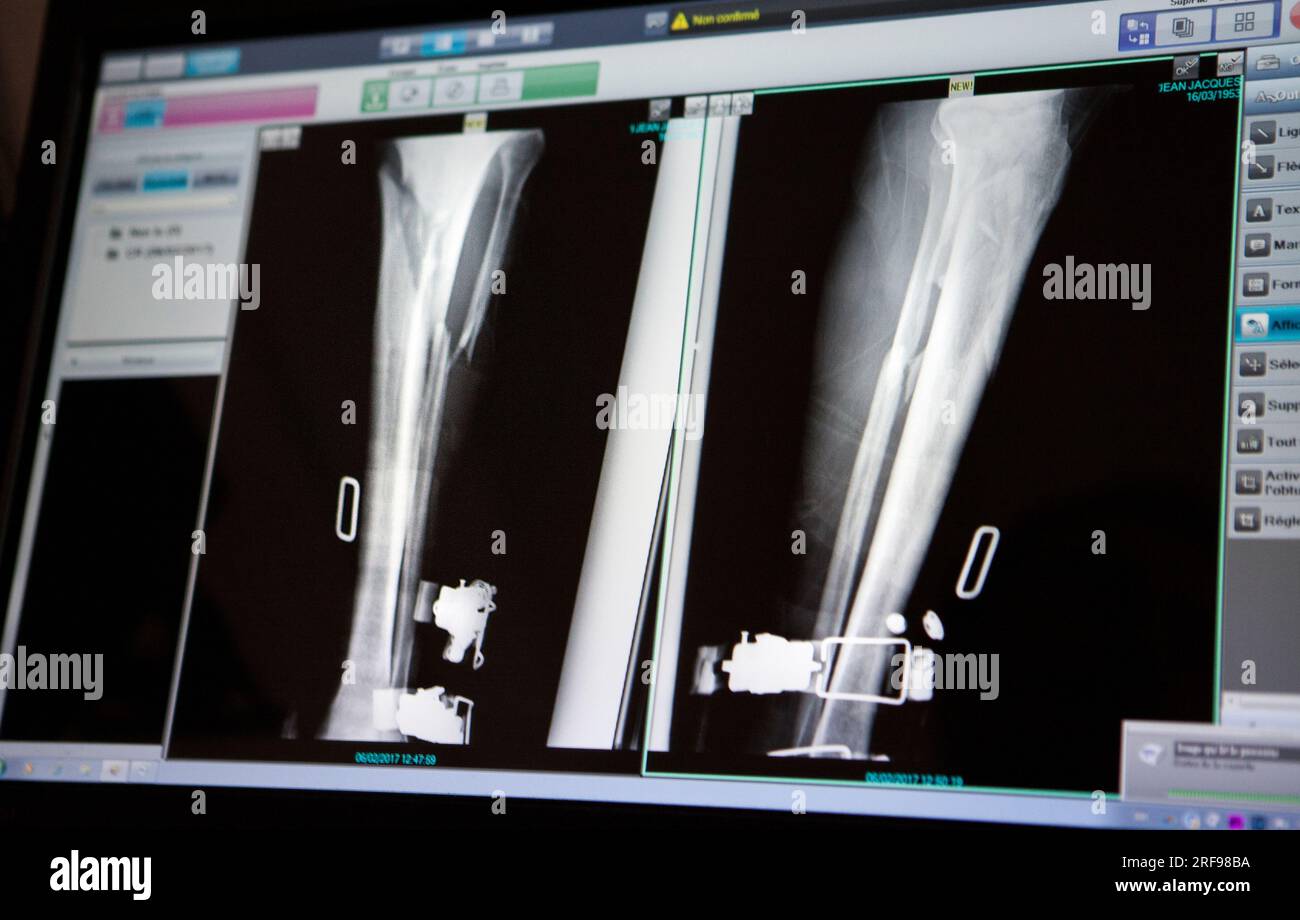

From www.alamy.com

Fracture of tibia and fibula hires stock photography and images Alamy Skiing After Tib Fib Fracture Also tore my calf in the process. They broke inside my boot, close to my ankle. i had a ski accident on feb 25th 2018 that resulted in compound fracture of tibia and fibula. i fractured my tibial plateau in 2 places feb 2016 at deer valley. rehabilitation guidelines for tibial plateau fracture. tibial plateau fractures. Skiing After Tib Fib Fracture.

Fracture of tibia and fibula hires stock photography and images Alamy Skiing After Tib Fib Fracture Also tore my calf in the process. Md follow up at 6 months. rehabilitation guidelines for tibial plateau fracture. i fractured my tibial plateau in 2 places feb 2016 at deer valley. i had a ski accident on feb 25th 2018 that resulted in compound fracture of tibia and fibula. They broke inside my boot, close to. Skiing After Tib Fib Fracture.